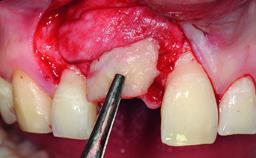

Replacement of an Upper Right Central Incisor with Root Resorption: Ridge Preservation, Early Placement of an RC Bone Level Implant

A 49-year-old female patient was referred for implant therapy to replace the upper right central incisor (tooth 11). The tooth had been assessed by an endodontist who diagnosed a vertical fracture of the root. The tooth had a hopeless prognosis and needed to be extracted. The patient was healthy and was not taking any medications. She was allergic to penicillin. The patient had high esthetic demands but her expectations were realistic. The extraoral examination revealed no facial asymmetries. The right temporomandibular joint demonstrated an opening click but was otherwise asymptomatic. The lip line was high with a significant gingival display.

Bone Augmentation Simultaneous|Vertical

Augmentation Materials Autogenous chips|Xenogenous|Membrane

Bone Volume Deficient vertically or deficient vertically AND horizontally